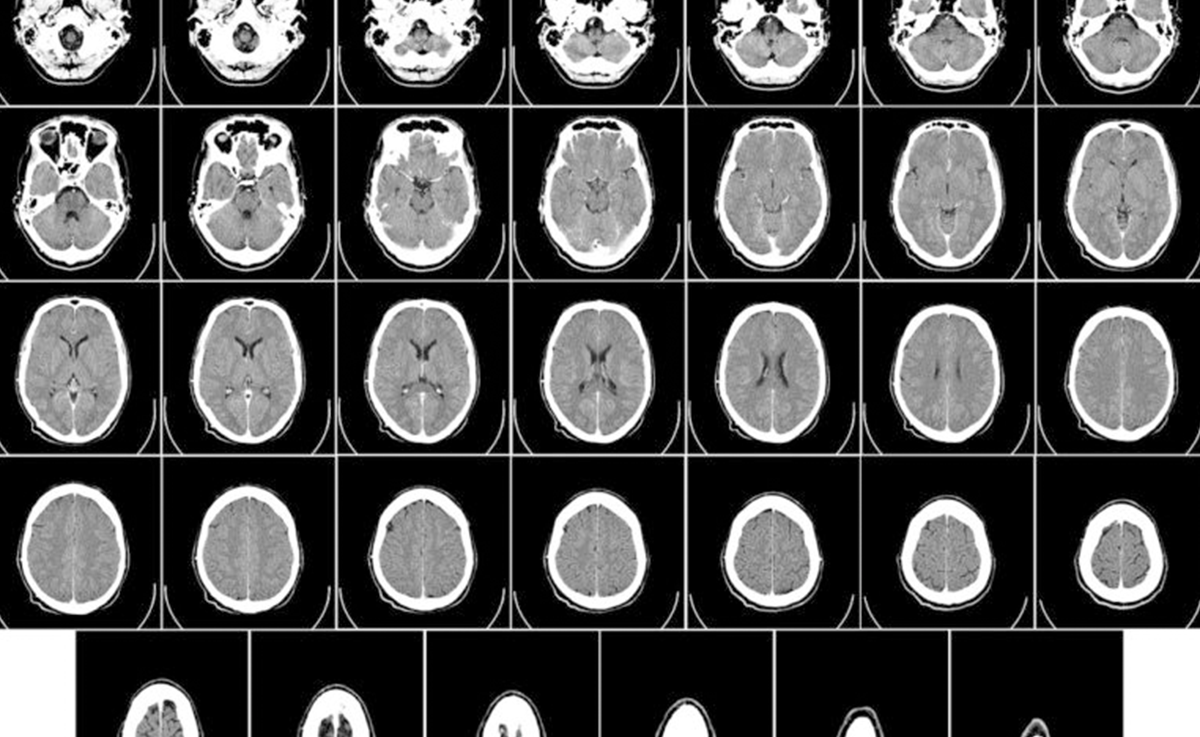

Рентген, компьютерная томография, МРТ, маммография — в медицине используют целый ряд визуальных инструментов диагностики. А специалисты по Data Science давно работают над автоматизацией определения болезней.

Уже сейчас алгоритмы нейросетей помогают диагностировать заболевания мозга, легких и сердечно-сосудистой системы. Есть множество проектов, ориентированных на распознавание проблем со здоровьем: BrainWeb, IXI Dataset, fastMRI, OASIS.

Обученные на сотнях тысяч примеров алгоритмы за несколько секунд делают работу, на которую даже опытному медику нужно минимум полчаса. Точность анализа удивляет — нейросеть способна найти болезни даже на начальных стадиях, задолго до первых симптомов.